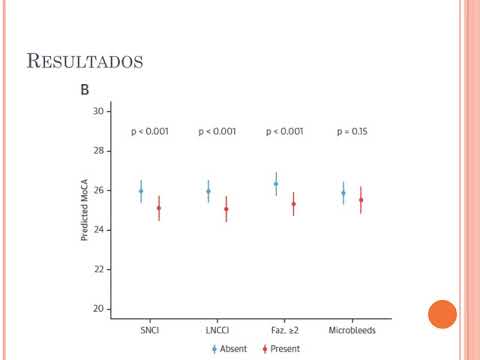

Relación entre lesiones cerebrales manifiestas y silentes con función cognitiva en pacientes con FA. Dra. Florencia Cichello. Residencia de Cardiología. Hospital C. Argerich. Buenos Aires